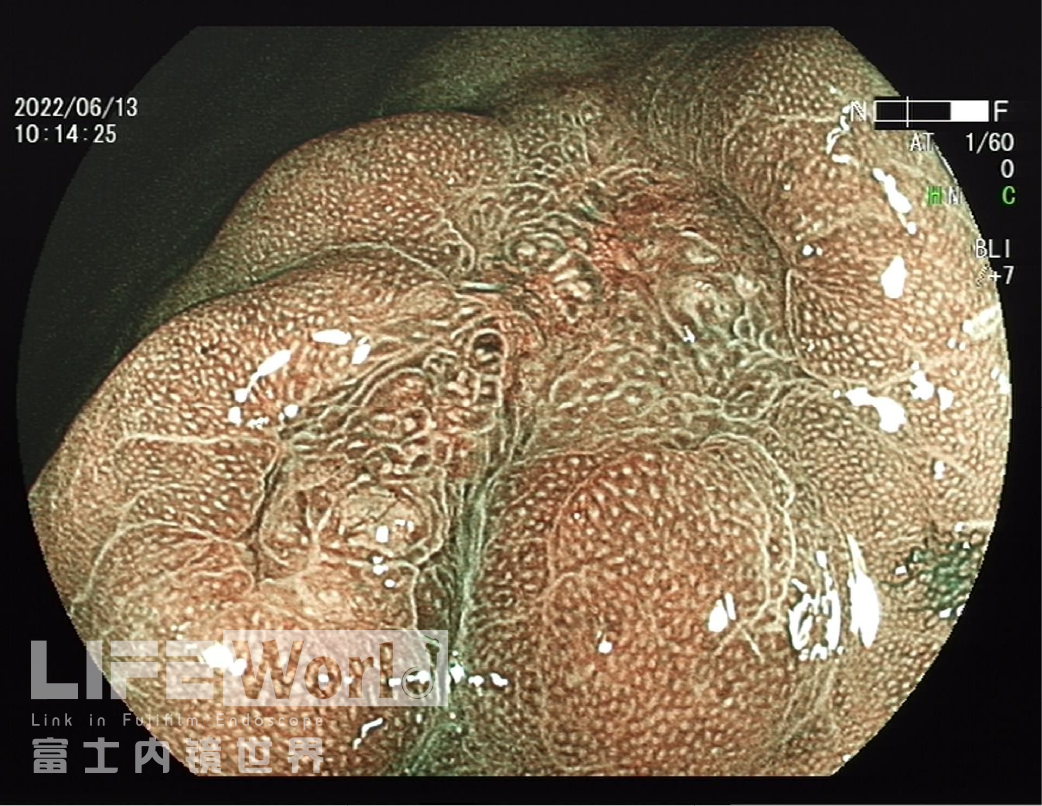

BLI模式低倍放大观察,可清晰的勾勒出病变的范围,病变的口侧端表面微结构的异型性明显,考虑为癌灶,病变的肛侧端异型性不明显,考虑为上皮内瘤变。

对考虑为癌灶的区域进行中倍放大观察:IMSP(+), IMVP(+)。